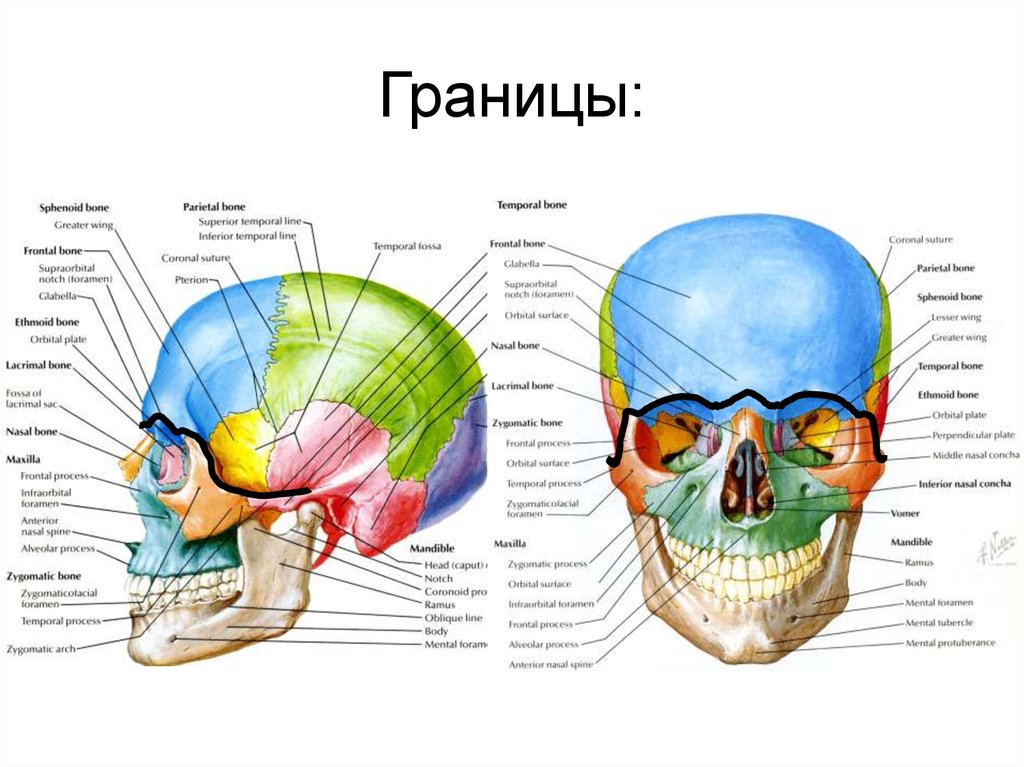

Анатомические детали: Фотографии топографии черепа с нижнего вида

Раздел: Альбом идей